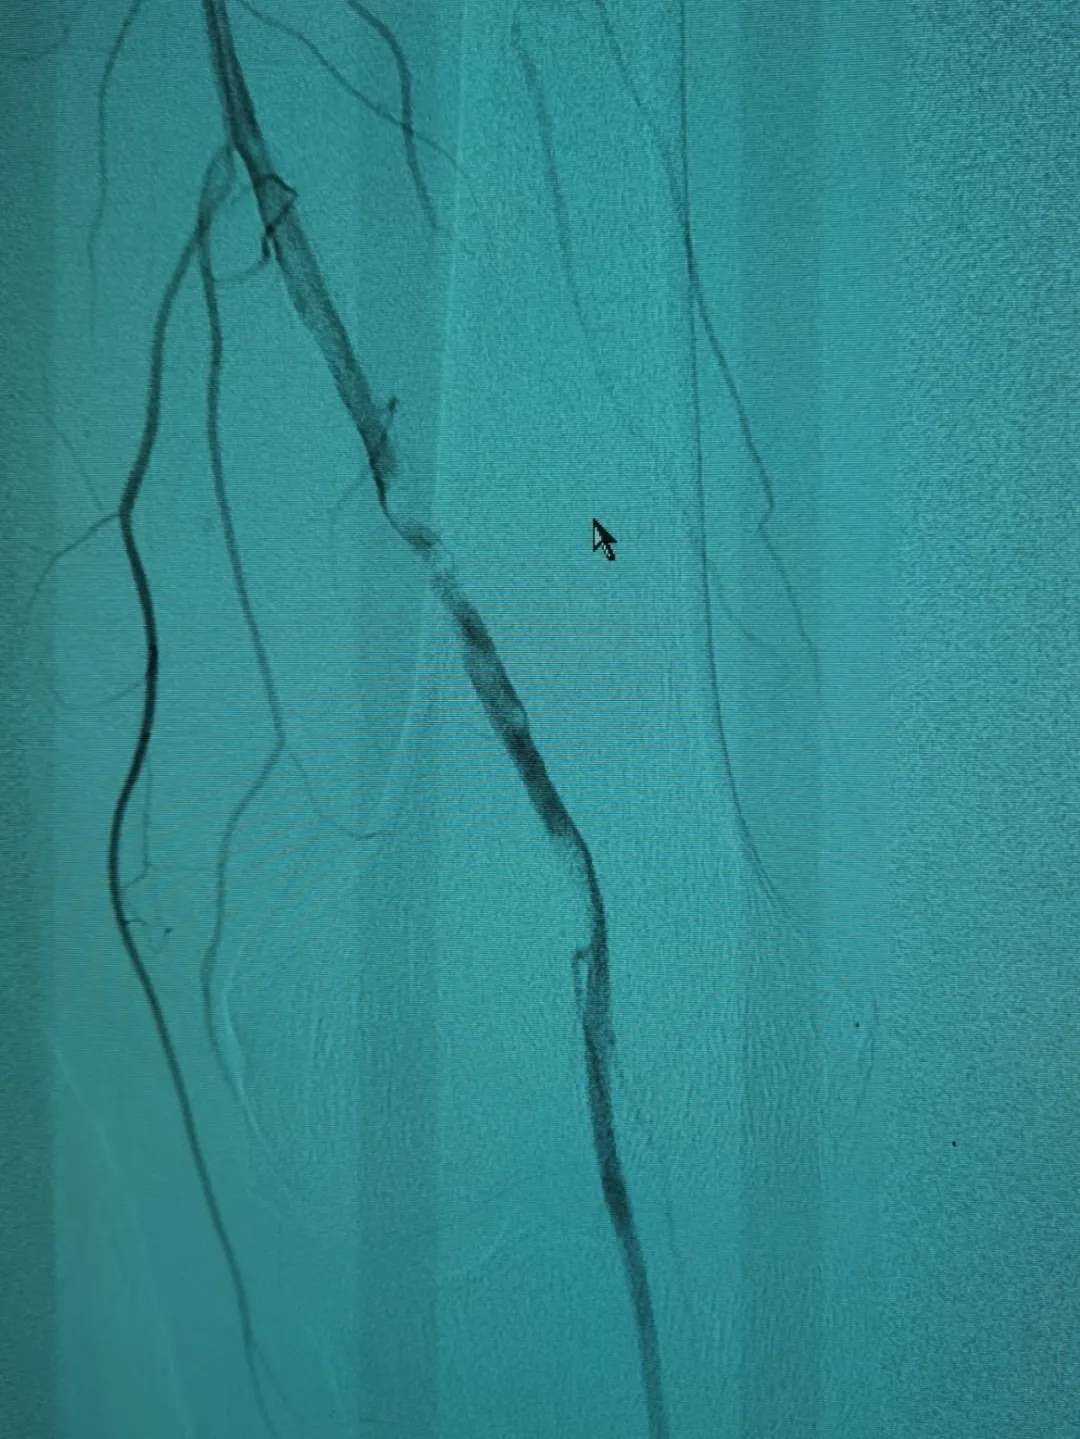

3月中旬,家人帶其到我院神經(jīng)外科治療。“根據(jù)患者的描述,是非常典型的間歇性跛行,我們給他做了雙下肢的血管造影,進一步證實了這一點。”施宏飛主任說,通過影像學(xué)檢查發(fā)現(xiàn),患者血管存在嚴(yán)重鈣化的斑塊,且左側(cè)股總動脈下段中重度狹窄,左側(cè)股淺動脈下段重度狹窄。

將這些動脈斑塊清除之后,又利用球囊為患者進行血管擴張,病變血管形態(tài)改善良好,可以清楚看到血管內(nèi)大量增生內(nèi)膜被旋切出來,取出遠端保護傘可以看見大量過濾的內(nèi)膜組織。